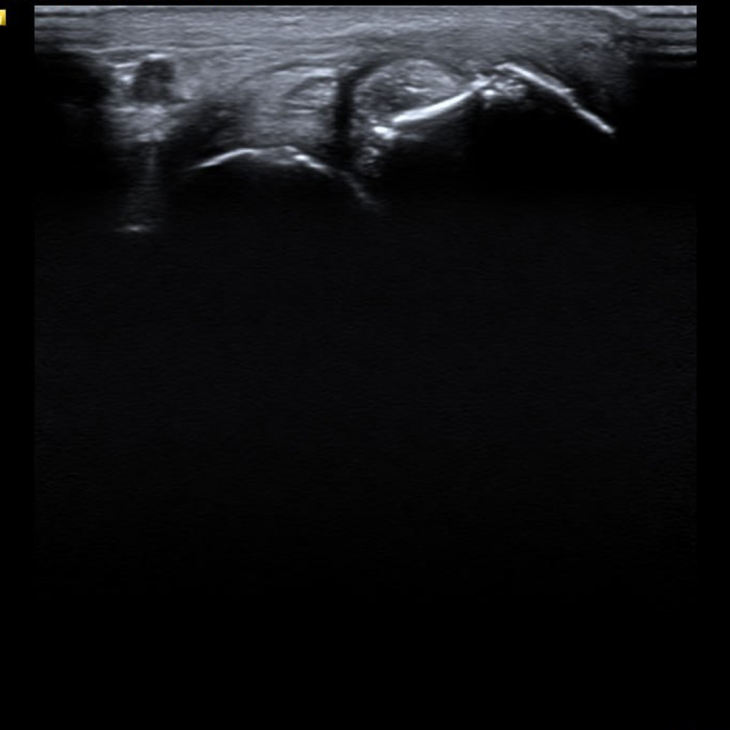

УЗД — чіткі ознаки структурного ураження:

• ерозії кістки;

• синовіт;

• випіт у суглобах.

Важливий момент: саме результати УЗД стали переломним фактором — пацієнт побачив реальні зміни й почав дотримуватися лікування.

УЗД дає можливість:

• виявити ураження раніше, ніж рентген;

• оцінити м’які тканини та ентезиси;

• контролювати активність запалення;

• підвищити довіру пацієнта до лікування.